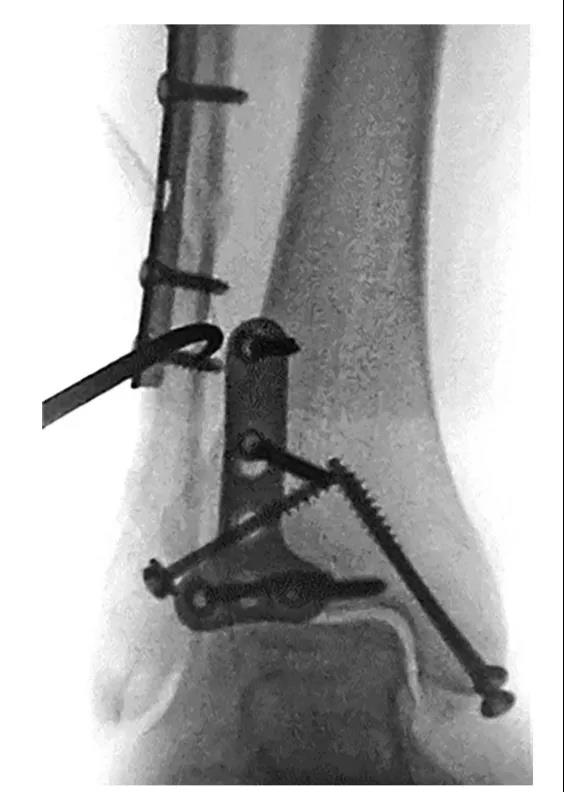

③ 首先俯卧位后外侧入路固定后踝,存在夹层骨块可行克氏针临时固定后抗滑钢板固定后踝。

④ 固定后踝后,经同一后外侧切口固定外踝,通常建议采用后侧钢板固定,如腓骨骨折线过高,则重新切口外侧钢板固定腓骨。⑤ 内踝常规切口固定内踝。⑥ 俯卧位患者屈曲膝关节,经前外侧切口固定前踝骨折块,通常选用2.7mm或3.5mm螺钉,并使用垫圈。